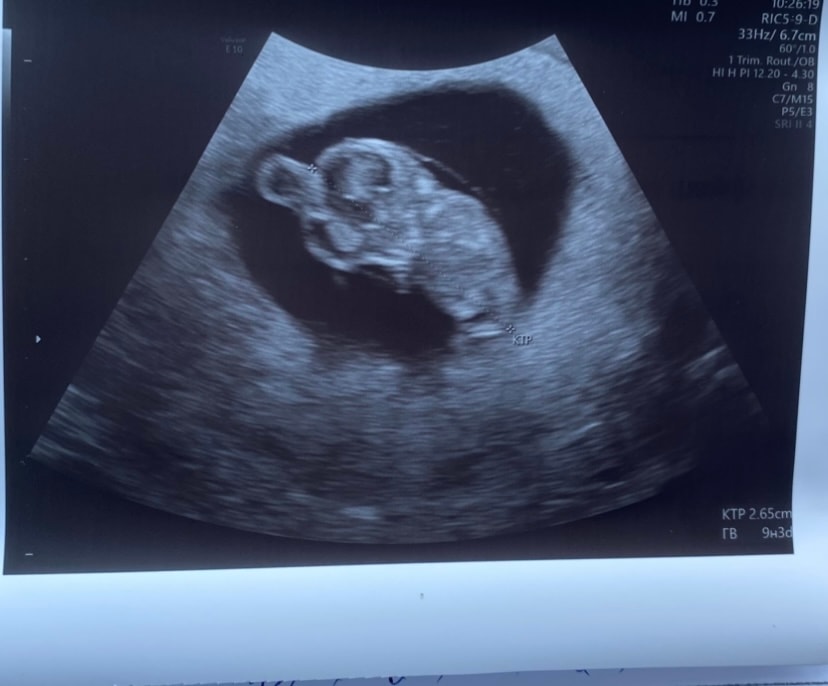

привет, девочки👋🏻🌸 нашли эмбрион и услышала сердечко❤️🥹 и такие данные:

СВД ПЯ 17 мм.

КТР эмбриона 3,3 мм

желточный мешочек 3,6 мм

ЧСС 118 уд/мин.

хорион локализация задняя стенка 5 мм. желтое тело в правом яичнике диаметром 13 мм.

врач сказала, что все соответствует сроку 6 недель и все хорошо🙌🏻 а я умная такая🫠😂 вычитала в гугле что ктр немн